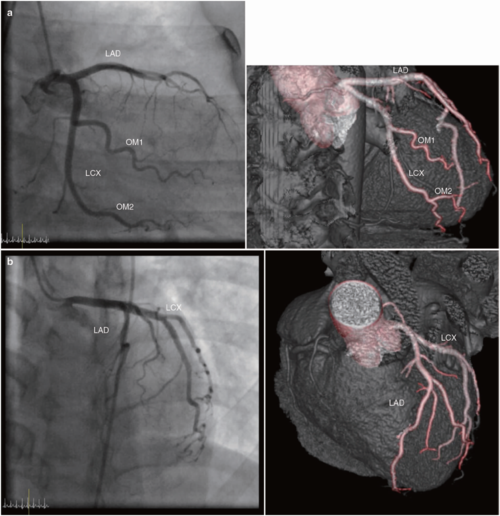

ct和mri如何看正常及异常冠状动脉,高清图谱请收好!

冠状动脉CT解剖

冠状动脉造影